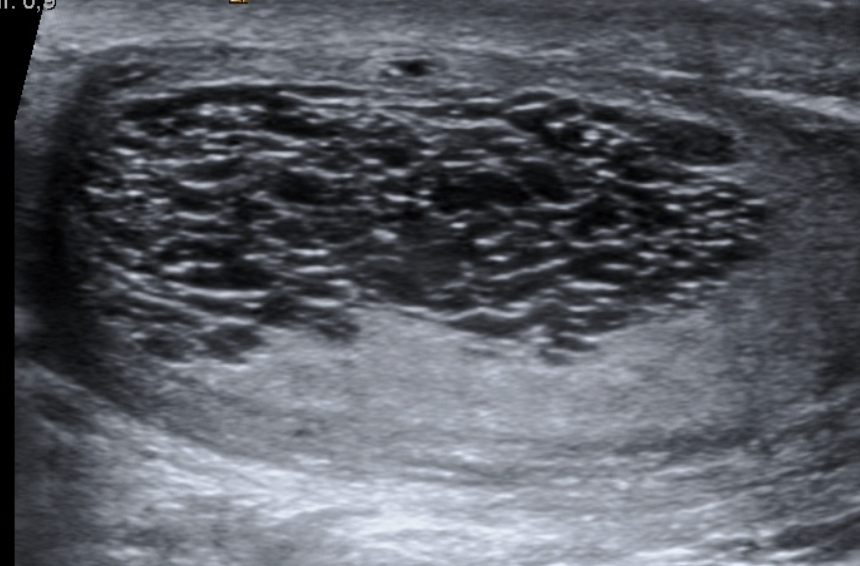

What are the sonographic findings in testicular torsion?

Enlarged, hypoechoic or heterogeneous testis with decreased or absent intratesticular blood flow.